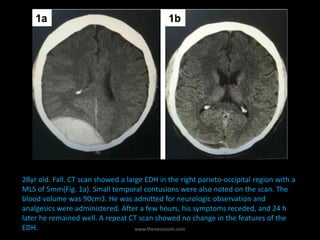

28yr old. Fall. CT scan showed a large EDH in the right parieto-occipital region with a

MLS of 5mm(Fig. 1a). Small temporal contusions were also noted on the scan. The

blood volume was 90cm3. He was admitted for neurologic observation and

analgesics were administered. After a few hours, his symptoms receded, and 24 h

later he remained well. A repeat CT scan showed no change in the features of the

EDH. www.theneurosim.com